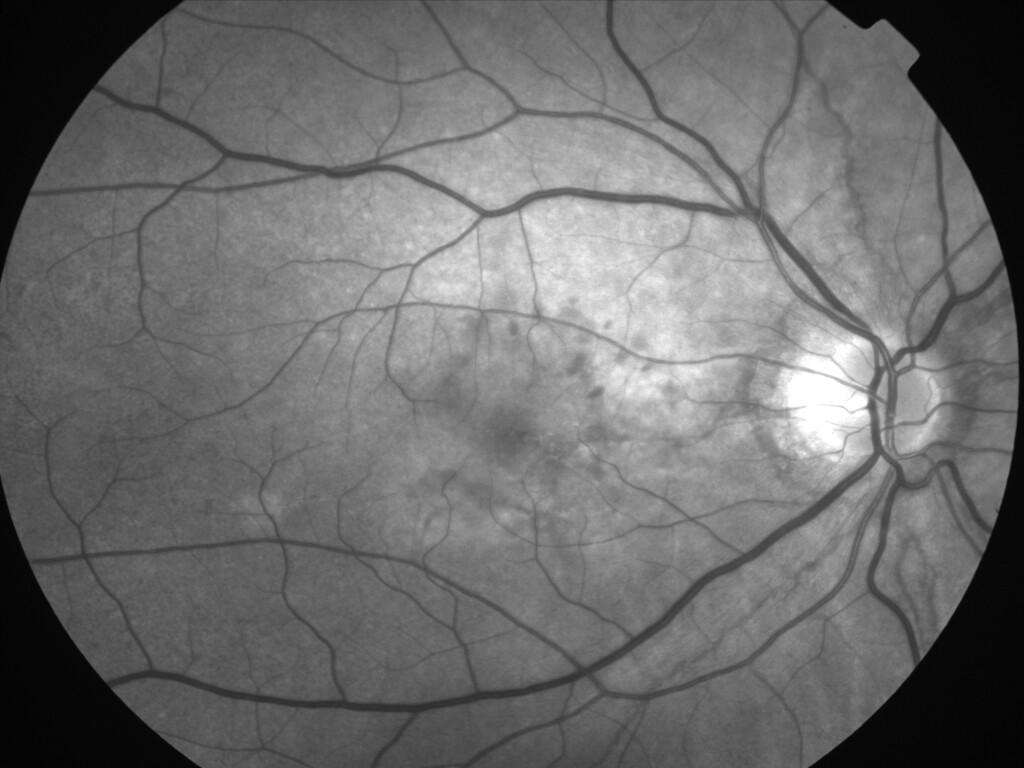

ASSOCIATION STRIES ANGIOIDES ET DYSROPHIE MACULAIRE RETICULEE

NEOVASCULARISATION